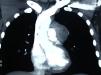

La paciente refería un episodio de hemoptisis autolimitada un mes antes, pérdida de peso que relacionaba con ansiedad, opresión retroesternal ocasional acompañada de parestesias en brazo izquierdo y episodios de broncoespasmo. Los estudios de laboratorio fueron normales. La tomografía computarizada torácica (fig. 1) informó como sigue: masa de partes blandas en mediastino anterior, de 5cm de diámetro, que ocupaba el espacio prevascular y ventana aortopulmonar. Dicha lesión sugería en primer lugar timoma o linfoma.